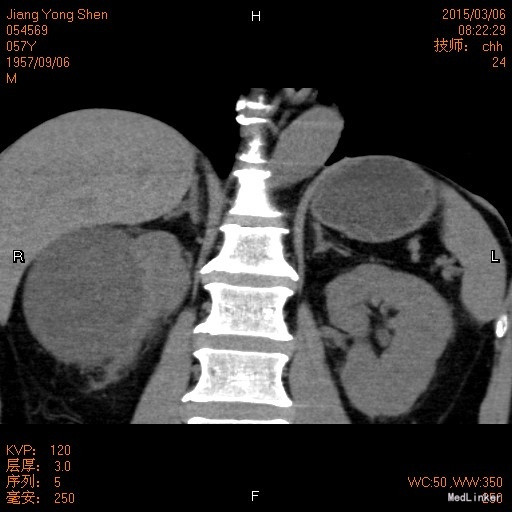

查体:双肾区无隆起,无压痛及叩击痛,双输尿管行程及双肋脊点、肋腰点无压痛及反跳痛,膀胱区无隆起, 叩诊空虚,无压痛。双侧阴囊皮肤无红肿。外生殖器正常。直肠指检未查。 辅助检查:2015-3-6我院CT:1.双侧肾上腺CT扫描未见明确异常。 2.右肾多发囊肿,其中一囊肿较大。 3.双肾中下盏多发小结石。 4.未排除肝脏多发小囊肿。

右肾囊肿 腹腔镜下右肾囊肿去顶术 麻醉成功后,停留尿管,取左侧卧位,常规消毒铺巾术野。于腋中线上髂嵴上方2cm,切皮肤约2cm,以刀柄顺肌纤维方向钝性分离达腰背筋膜 ,撑开腰背筋膜入腹膜后间隙,扪及腰大肌后,用食指将腹膜及其内脏器尽量推开,置入自制气囊注入约900ml空气撑开腹膜后空间后,手指引导下于12肋缘下腋前、后线处分别置入5mm,5mm套管,置入腹腔镜观察各操作通道位置,完成腹膜后工作空间的创建。清理腹膜外脂肪,打开肾周筋膜,游离肾周脂肪,见囊肿大小约8cm,游离囊壁脂肪及肾包膜,打开囊壁,吸尽囊液,减除无肾组织部分完整囊壁送检,超声刀止血切缘,腹膜后置F16肾造瘘管1条以作引流,清点器械无误,逐层缝合切口